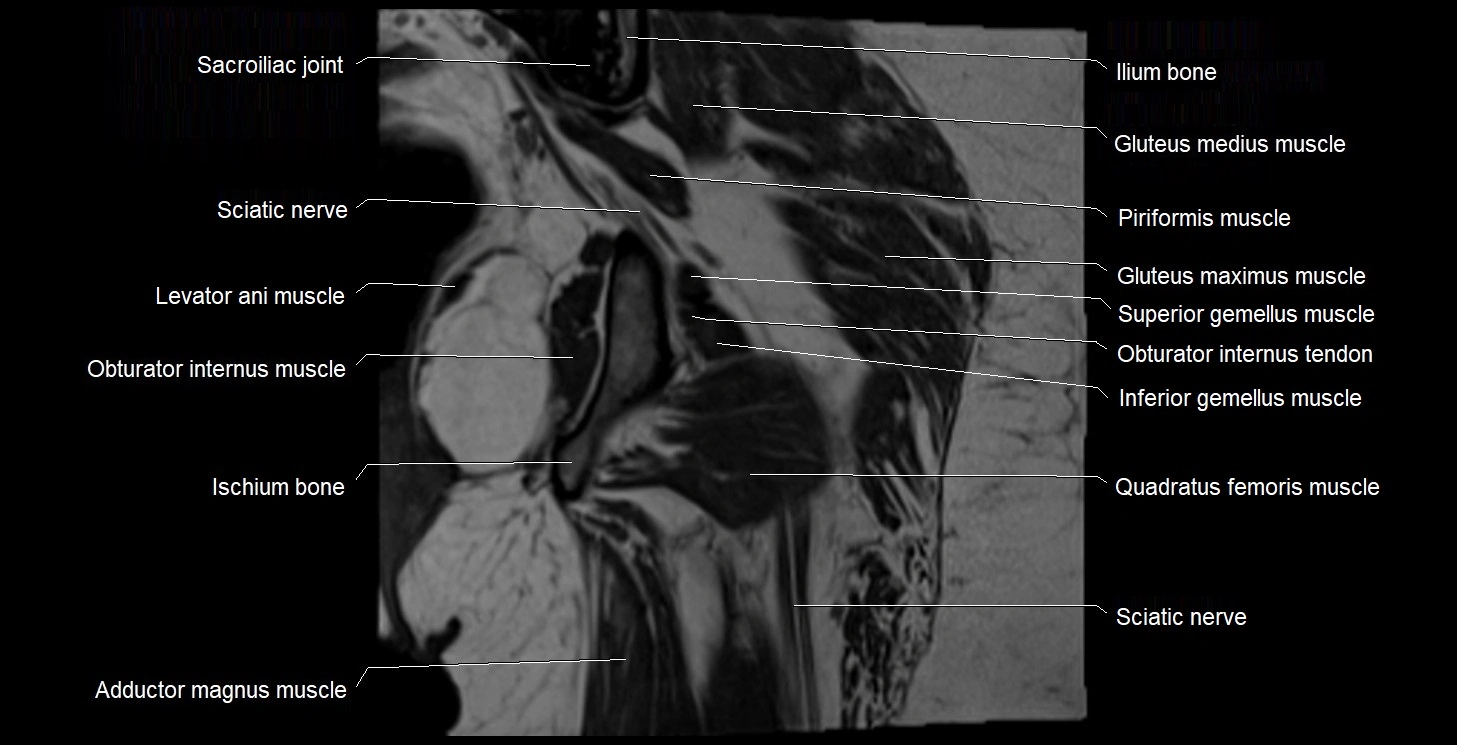

- Adductor magnus muscle

- Coccygeus muscle

- Gluteus maximus muscle

- Gluteus medius muscle

- Gluteus minimus muscle

- Ilium bone

- Inferior gemellus muscle

- Ischial tuberosity

- Ischium bone

- Levator ani muscle

- Obturator internus muscle

- Obturator internus tendon

- Quadratus femoris muscle

- Sacral plexus

- Sacroiliac joint

- Superior gemellus muscle